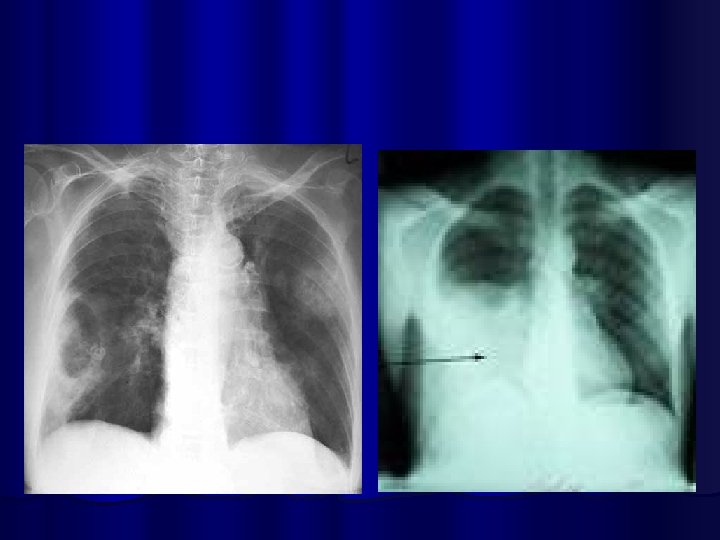

Lung Abcess Empyema

COMPLICATIONS OF PNEUMONIA l Parapneumonic effusion l Empyema l Sepsis l ARDS l Lung abcess l Focal Bronchiectasis